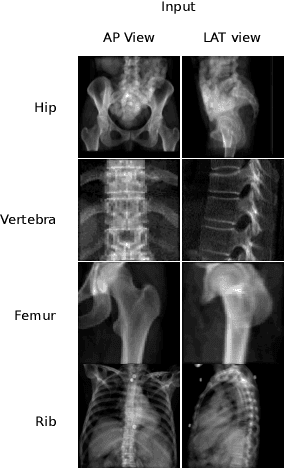

Various deep learning models have been proposed for 3D bone shape reconstruction from two orthogonal (biplanar) X-ray images. However, it is unclear how these models compare against each other since they are evaluated on different anatomy, cohort and (often privately held) datasets. Moreover, the impact of the commonly optimized image-based segmentation metrics such as dice score on the estimation of clinical parameters relevant in 2D-3D bone shape reconstruction is not well known. To move closer toward clinical translation, we propose a benchmarking framework that evaluates tasks relevant to real-world clinical scenarios, including reconstruction of fractured bones, bones with implants, robustness to population shift, and error in estimating clinical parameters. Our open-source platform provides reference implementations of 8 models (many of whose implementations were not publicly available), APIs to easily collect and preprocess 6 public datasets, and the implementation of automatic clinical parameter and landmark extraction methods. We present an extensive evaluation of 8 2D-3D models on equal footing using 6 public datasets comprising images for four different anatomies. Our results show that attention-based methods that capture global spatial relationships tend to perform better across all anatomies and datasets; performance on clinically relevant subgroups may be overestimated without disaggregated reporting; ribs are substantially more difficult to reconstruct compared to femur, hip and spine; and the dice score improvement does not always bring a corresponding improvement in the automatic estimation of clinically relevant parameters.